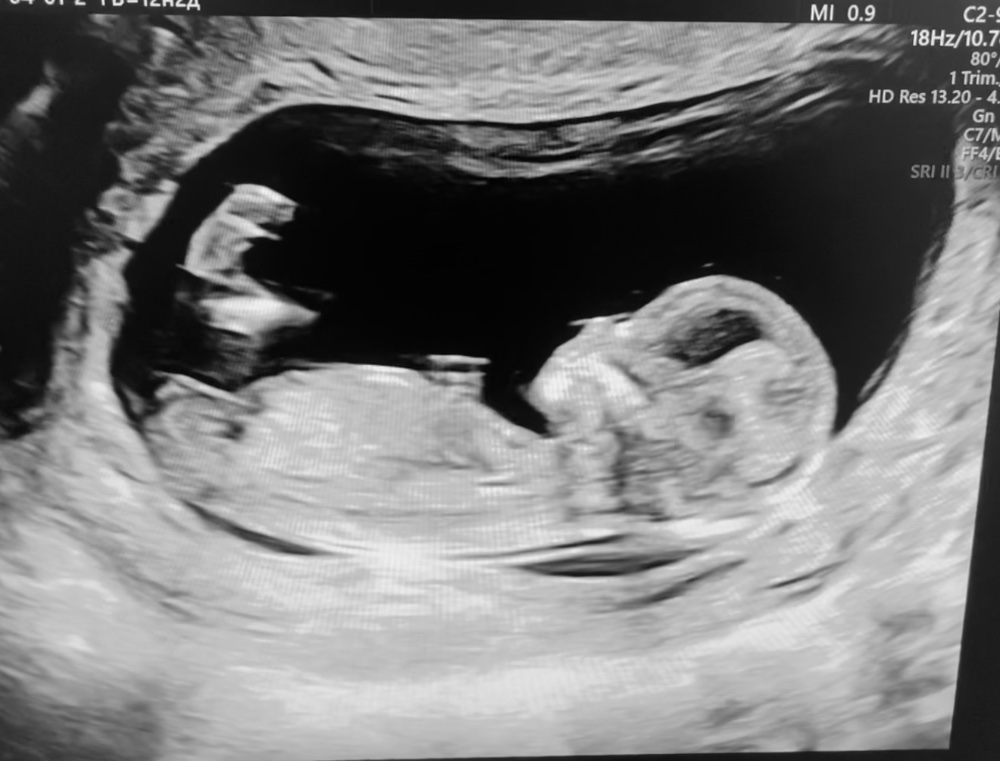

11 недель 4 дня, половой бугорок, узи

Девочки, была на приеме у гинеколога, она мне быстренько малявку посмотрела, чтоб до скрининга я спокойна была.

Ну и заодно пол предположила. Очень обнадежила, что бугорком похож на мальчика.

Тут видно только ножки. Полосой бугорок на этом сроке очень похож у девочки и мальчика. У мальчика он только-только начинает приподниматься. Вот мальчик срок 11.1

На этом фото не видно бугорка, но раз узист сказала что бугорком на мальчика похож , думаю процентов 80 есть что мальчик 🙏

Мария, она мне что-то там показывала на мониторе, но я так ничего и не поняла 😅 с дочками все же побольше немного срок был, да и аппарат узи гораздо лучше, картинка совсем другого качества была